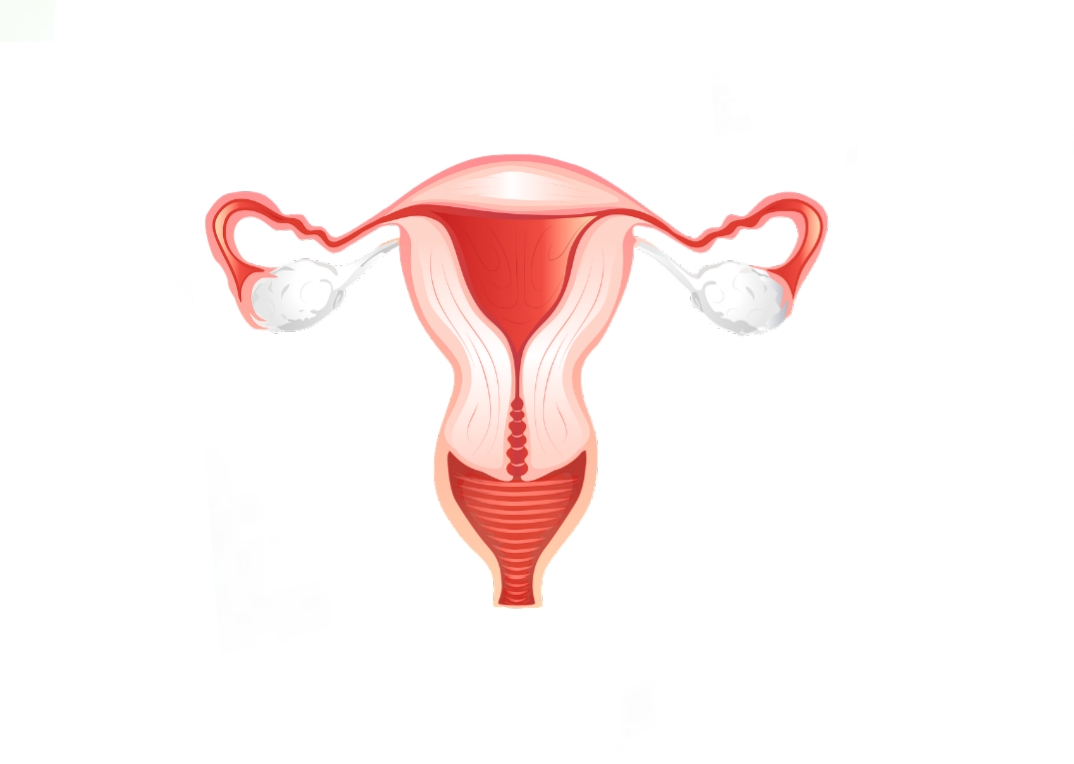

Анатомия женского организма: строение и функции матки

Раздел: Фотопуть к знанию